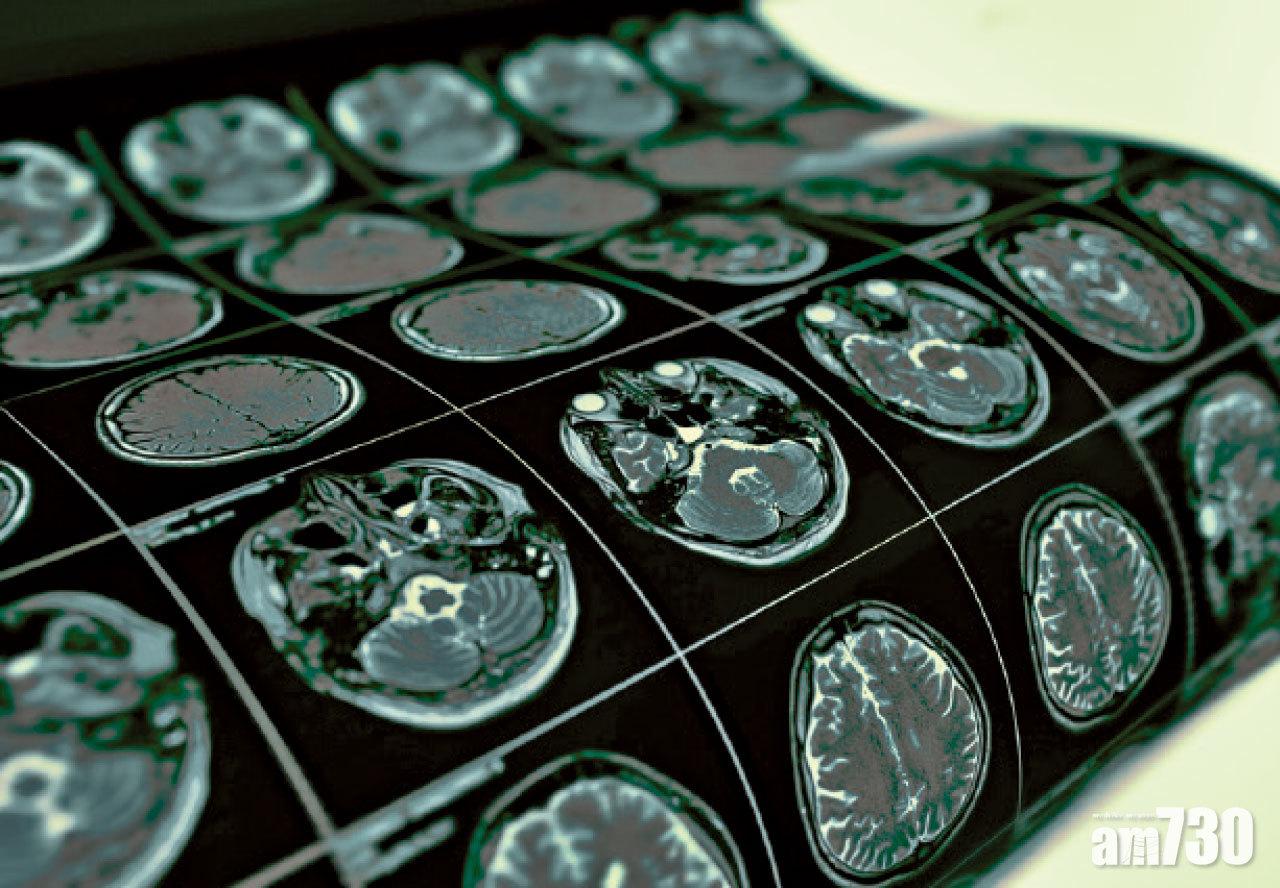

除非屬認知障礙初期,否則面診一般較難分辨為哪一類,莊麗表示,「阿茲海默症一般短期記憶影響較多,而血管性認知障礙的行政能力及處理速度會較差,反應、『轉數』較慢。如果走路慢、一邊身體感覺和力量較差、有三高問題都是一些線索讓醫生作估算。深入檢查如用磁力共振照腦部結構、血管阻塞情況,以及用3D磁力共振計算海馬體體積等,就可以清晰地告知患者屬哪一類認知障礙。」

磁力共振檢查腦部,有助確診認知障礙症。